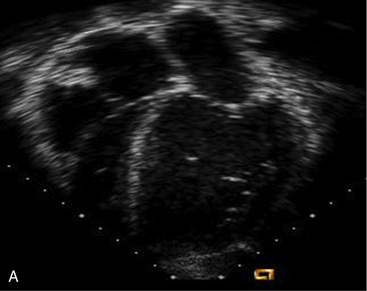

The echocardiogram is required to rule out the presence of structural heart disease, and it will enable evaluation of heart size, ventricular contractility, and atrioventricular (AV) valve function. The echocardiogram also will confirm the presence of any significant pericardial effusion.

The echocardiogram demonstrates ventricular dilation, disproportionate ventricular septal thickening, or possible obstruction of the left and/or right ventricular outflow tracts. Echocardiographic findings show globally decreased contractility without regional wall motion abnormalities. Color and pulse-wave Doppler can determine the presence and degree of valve regurgitation, assess cardiac output by aortic flow velocities, determine the degree of diastolic dysfunction by atrioventricular (AV) valve inflow pattern, and estimate pulmonary artery and right ventricular pressures. Echocardiography is beneficial for monitoring patients longitudinally as well as for detecting changes in ventricular function, thrombus formation, wall stress, pulmonary vascular disease, and valvular regurgitation.212